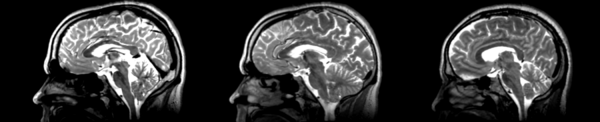

- 01053-t2 -> 01031-t2 = Result. All the images shown have the moving image on the left, the resultant image in the middle, and the target image on the right.

Rigid

01053>01031rigid.png = not bad... different brains of different sizes, but seem to be aligned in the ventricles so output seems okay. output slightly blurry. bad initial leveling displays.

Linear

01053>01031linear.png = not bad... different brains of different sizes, but seem to be aligned in the ventricles so output seems okay.output slightly blurry. bad initial leveling displays.

Affine

01053>01031_affine.png = looks good in terms of size. odd warping of frontal lobe and cerebellum area, but otherwise good coregistration.

B-spline

01053>01031_bspline.png = looks good in terms of size. odd warping of frontal/temporal lobe and cerebellum area, but otherwise good coregistration.

Diffeomorphic Demons

01053>01031_demons.png = 10 minutes. Window/leveling initially off. Otherwise, it looks really good. Not much distortion.